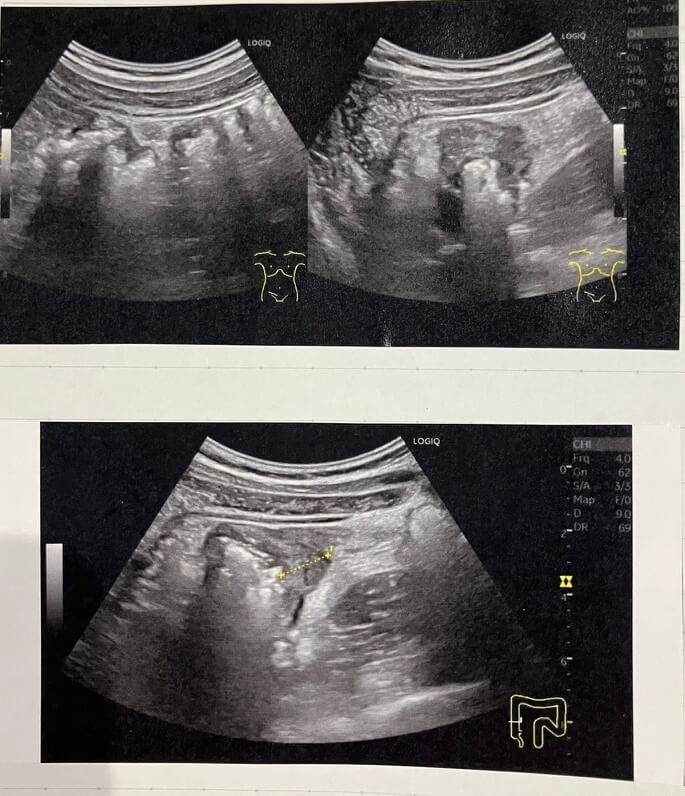

【腹部エコー】症例4 憩室炎

今回は憩室炎の症例です。

とりあえず痛みのある部位にエコーを当てると、上行結腸壁の限局性の低エコー肥厚を認めます。

周囲脂肪織のエコー輝度上昇もあります。

カラードプラで血流をみましたが、カラー乗りません。

大腸壁の限局性の肥厚で、周囲脂肪織の上昇って言ったら、憩室炎を考えるけれど…。でも、いつもよく遭遇するような憩室炎っぽくはない…。

大腸から飛び出しているあのエコー像が描出できないなぁ。。とちょっと悩んで…

右下腹部付近を走査すると、、回盲部付近にリンパ節の腫大が軽度あるではないですか…。

仕方なしに、Drに痛みの部位の上行結腸壁に限局性肥厚と周囲炎症像がありますが、はっきりとした憩室は分かりません。虫垂は描出できません。と報告しました。

他院のCT結果が返ってきてたので確認すると、『憩室と大腸壁浮腫』との診断で結果が返ってきておりました。